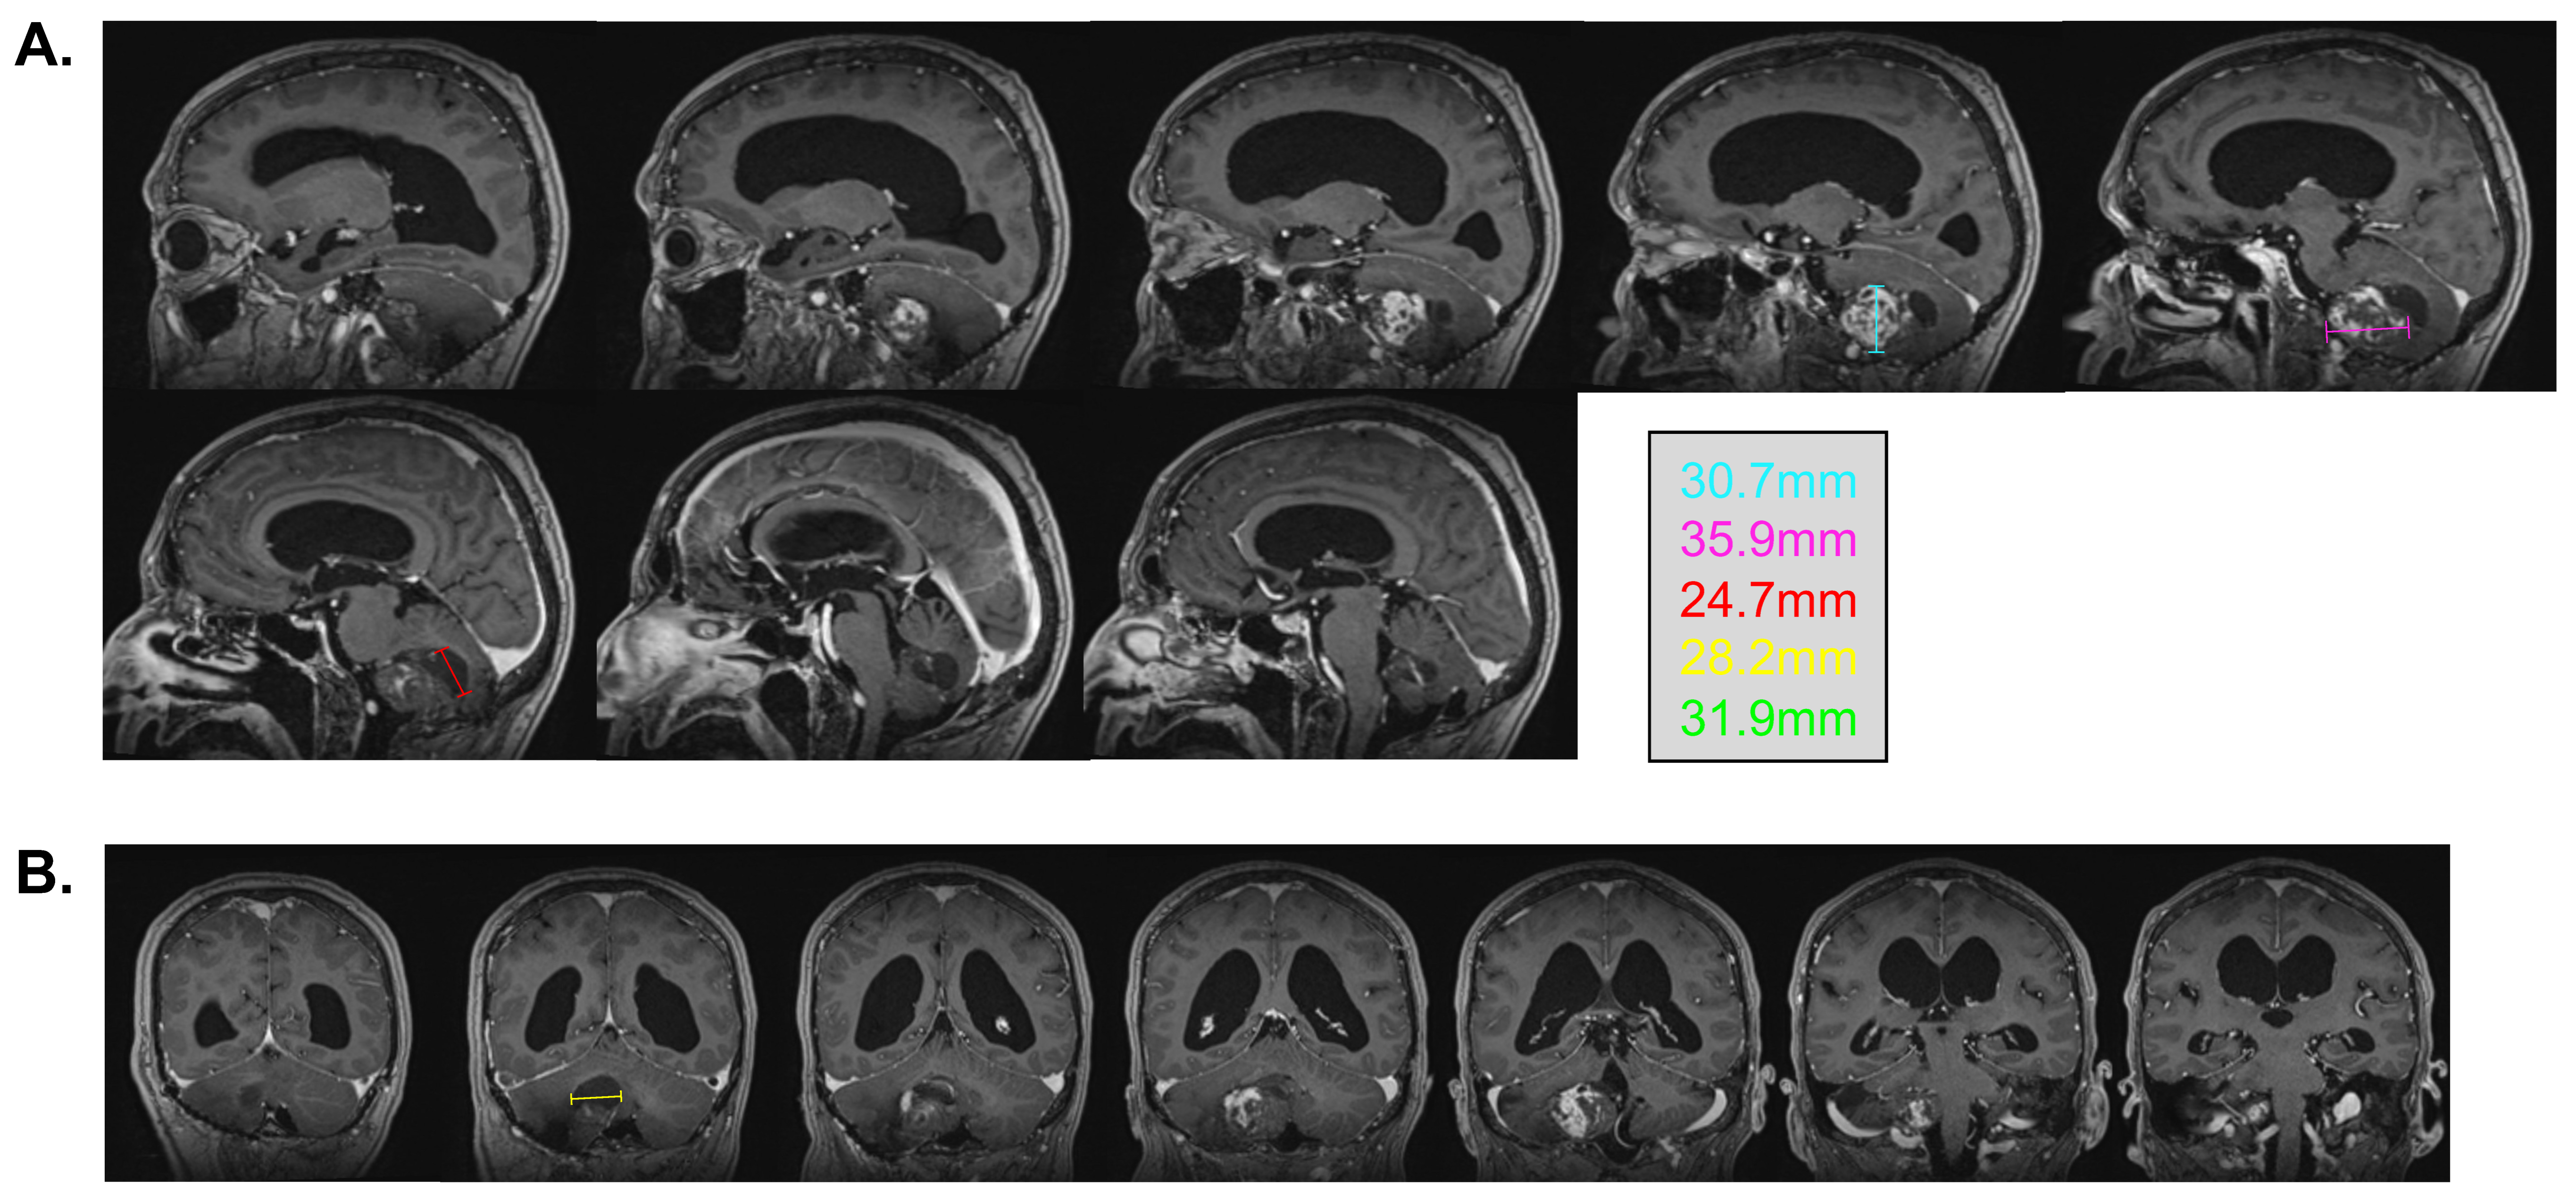

In 2007, a 2 cm progressing enhancing lesion was found, which was stable throughout 2008 and 2009. Minimal progression was again noted in 2010 and 2012. In September 2014, the enhancing portion of the lesion was noted as progressing from 19 × 12 × 15 mm to 20 × 15 × 16 mm (anteroposterior, transverse, cranio-caudal, respectively). A de novo circular, fluid-filled lesion was also noted anteriorly, measuring 8.1 × 15.2 × 13 mm. At the time of radiosurgery planning, the overall lesion measured 25 × 15 mm (AP, T, respectively), with the presence of solid as well as fluid components (Figure 1A).

Radiosurgery for the slowly progressing lesion was recommended at the neuro-oncology tumor board, primarily because of the deep location of the lesion and its relapsing nature. The procedure took place on 17 December 2014. Immobilization was performed using a stereotactic frame, and an axial MRI T1 post-gadolinium sequence was fused to the planning CT scan for delineation of the target. A dosimetric plan was obtained using the X-Knife treatment planning system. SRS was delivered on a Varian Trilogy unit equipped with a high-definition multi-leaf collimator. The patient received an SRS of 18 Gy, which was prescribed at the 87% isodose, considering that the lesion was situated at millimetric distance to the brainstem to optimize the dose fall-off (Figure 1B). A total of 83% of the tumor volume was covered by the 18 Gy isodose, and 99.9% was covered by the 15 Gy isodose. The gross tumor volume (GTV) was 3.77 cm3. The treatment volume ratio (TVR) was 1.2, and the prescription isodose to target volume (PITV) was 1.0. The maximal point dose to the brainstem was 13.1 Gy. The volume of normal brain that received 12 Gy was 7.9 cm3.

Figure 1. Stereotaxic radiosurgery planification. (A) Cerebral MRI T1 images prior to stereotactic radiosurgery, with a demonstration of the polylobulated lesion in the axial view, coronal view, and sagittal view. (B) Isodose coverage of the GTV (in red) for the 18 Gy radiosurgery plan. The blue contour is an expansion of 1 mm of the GTV treated at an 87% isodose because of the proximity with the brainstem. A total of 83% of the tumor volume was covered by the 18 Gy isodose, and 99.9% was covered by the 15 Gy isodose.